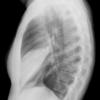

Case 3 RM & UL pneum Lat

Date: 07/04/2004

Views: 6896